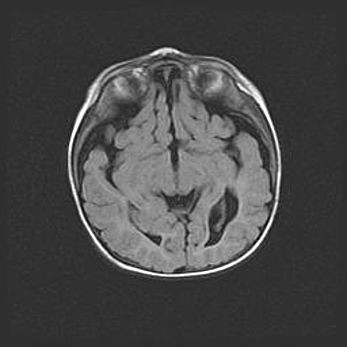

Открытая гидроцефалия.

Возраст: 6 месяцев 15 дней

Вес: 6200 г

Пол: женский

Окружность головы: 41 см

Срок гестации: 38 недель

Гидроцефалия головного мозга у новорожденных – это скопление избыточного количества цереброспинальной жидкости в головном мозге. Ее избыточное скопление в мозге приводит к патологическому расширению желудочков мозга (четырех полостей, расположенных в глубине белого вещества мозга, заполненных цереброспинальной жидкостью и связанных узкими проходами).

Открытый тип гидроцефалии (сообщающаяся) наблюдается тогда, когда нарушен механизм всасывания ликвора в системный кровоток. При этом типе причиной заболевания чаще всего является перенесенные ранее инфекции (например: менингит),  либо же наличие крови в субарахноидальном пространстве.